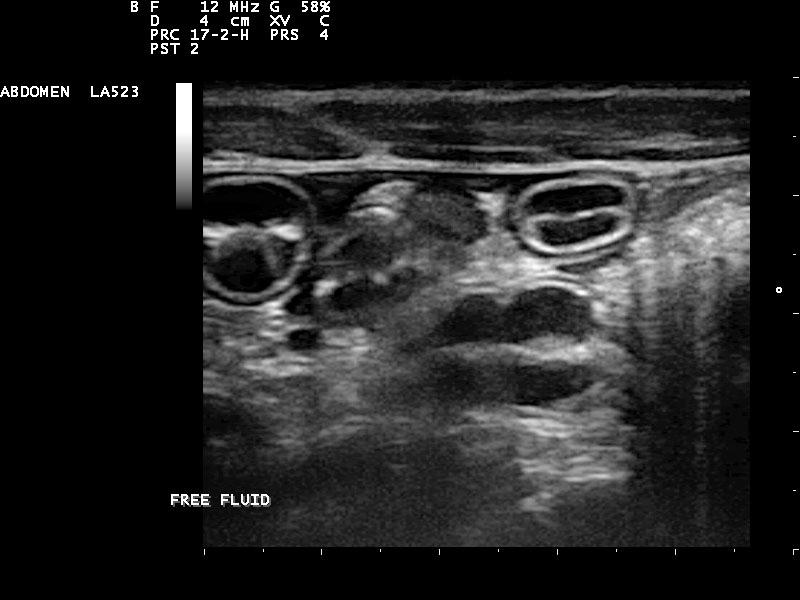

Diffuse nodular liver disease and microhepatica. The portal vein can be followed completely to its branches, but it is very tortuous and with the ascites that is seen, might be indicative of portal hypertension. This is typical cirrhosis with possible portal vein branch hypoplasia-microvascular dysplasia. The bile acids are likely very high and the clinical signs are owing to hyperammonemia. There are secondary shunts as well demonstrated by the tortuous vessels especially in the area of the pancreas where there is pancreatic edema. The lobe portal vein velocities support portal vein hypertension.